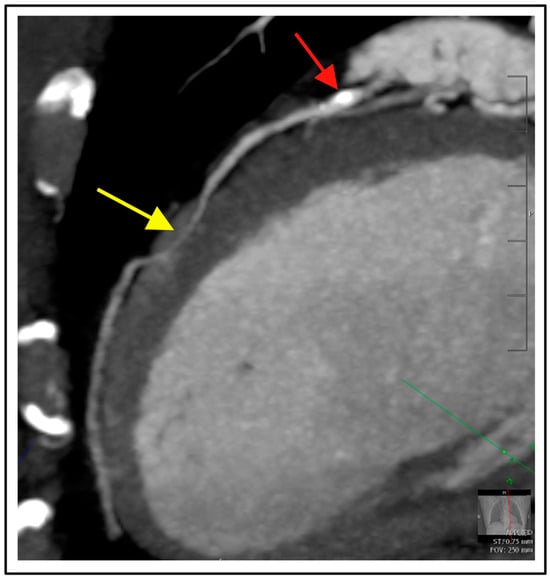

4. Functional Evaluation by CT

4.2. CT Perfusion Imaging (CTP)